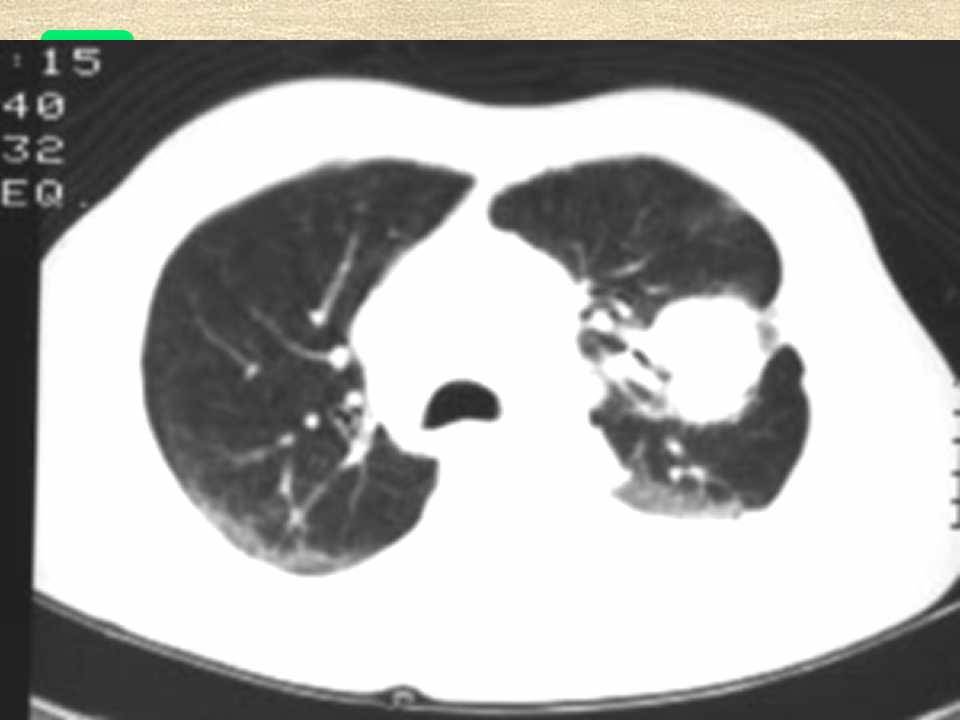

肺癌影像学表现